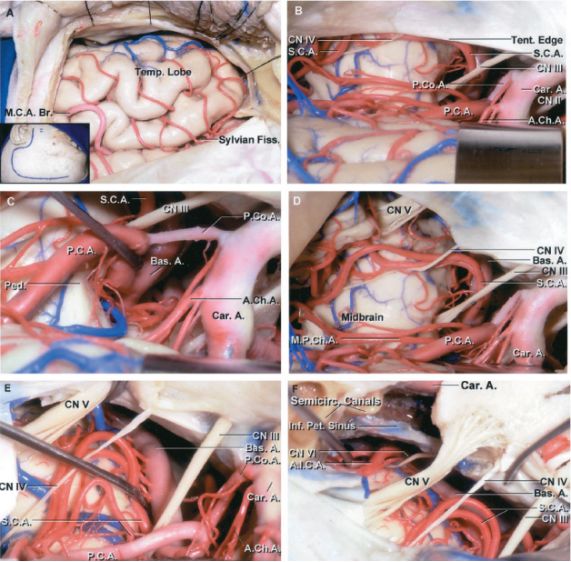

图2:图示经左侧颞下入路到达中脑周围与脚间窝(上图)。动眼神经是需早期辨认的一个重要解剖标志,可避免向后过度分离(下图)。切开天幕可扩大颞下入路,处理低位基底动脉分叉部动脉瘤(AL Rhoton, Jr惠赠图片)

注:MPChA:脉络膜后内侧动脉。Tent.Edge:天幕缘。P2p:大脑后动脉P2段后部。SCA:小脑上动脉。P2a:大脑后动脉P2段前部。Post.Seg.:丘脑穿动脉后段。Apex:基底动脉尖。CN Ⅲ:动眼神经。Bas.Tr.:基底动脉主干。P1:大脑后动脉P1段。PcoA:后交通动脉。ICA:颈内动脉。AchA:脉络膜前动脉。Ant.Set.:丘脑穿动脉前段。Ambient Cist.:环池。Crural Cist.:脚池。CN Ⅳ:滑车神经。Cerebellum:小脑。Colliculus:上丘。Basal V.:基底静脉。

图3:图示经左侧颞下入路到达基底动脉尖区域。中排左图清晰显示了神经血管的解剖关系。切开天幕(下排,左图)或磨除岩前骨质(下排,右图)可扩大显露范围(AL Rhoton, Jr惠赠图片)。注意,该通路观察对侧P1段的视野受限。动眼神经是该区域重要的解剖标记。

注:M.C.A.Br.:大脑中动脉分支。Temp.Lobe:颞叶。Sylvian Fiss.:侧裂。CN Ⅳ:滑车神经。S.C.A.:小脑上动脉。P.Co.A.:后交通动脉。P.C.A.:大脑后动脉。Tent.Edge:天幕缘。CN Ⅲ:动眼神经。Car.A.:颈内动脉。CN Ⅱ:视神经。A.Ch.A.:脉络膜前动脉。Ped.:大脑脚。Bas.A.:基底动脉。CN Ⅴ:三叉神经。Midbrain:中脑。M.P.Ch.A.:脉络膜后内侧动脉。Semicirc.Canals:半规管。Int.Pet.Sinus:岩下窦。A.I.C.A.:小脑前下动脉。